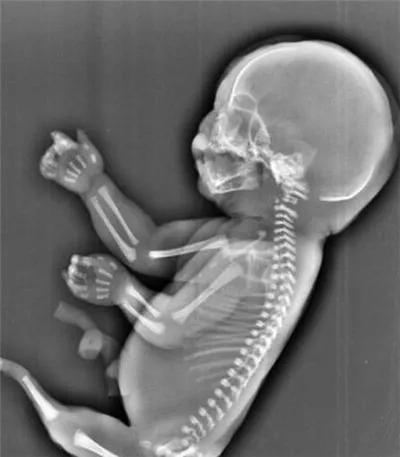

但世界上真的出生过美人鱼一样的婴儿,即上半身是正常的婴孩,下半身就像小美人鱼尚未劈开的双腿一样,是连在一起的。

而这些“小人鱼”的一生如此短暂。由于缺少肾脏之类的重要器官,这类婴儿出生后只能存活几个小时。

在人类的语言里,这叫“美人鱼综合征”。

“美人鱼综合征”,或称并腿畸胎综合征,是一种极其罕见的先天畸形,患病率约为十万分之一,和连体婴儿差不多。

一般情况下,胎儿在子宫内拥有两条脐动脉和一条脐静脉,但美人鱼综合征的孩子,只有一条脐动脉,他们的血液循环系统在早期就没有发育完全。

这条异常的脐动脉,会将供给胎儿下半身的血液和营养输送给胎盘,导致胎儿的下半身器官组织无法形成,双腿也无法正常分开。

也就是说,他们双腿黏连的原因,与大海和浪漫的美人鱼传说,没有一点关系。只是因为下半身发育不健全,维持早期胚胎形态直到出生而已。